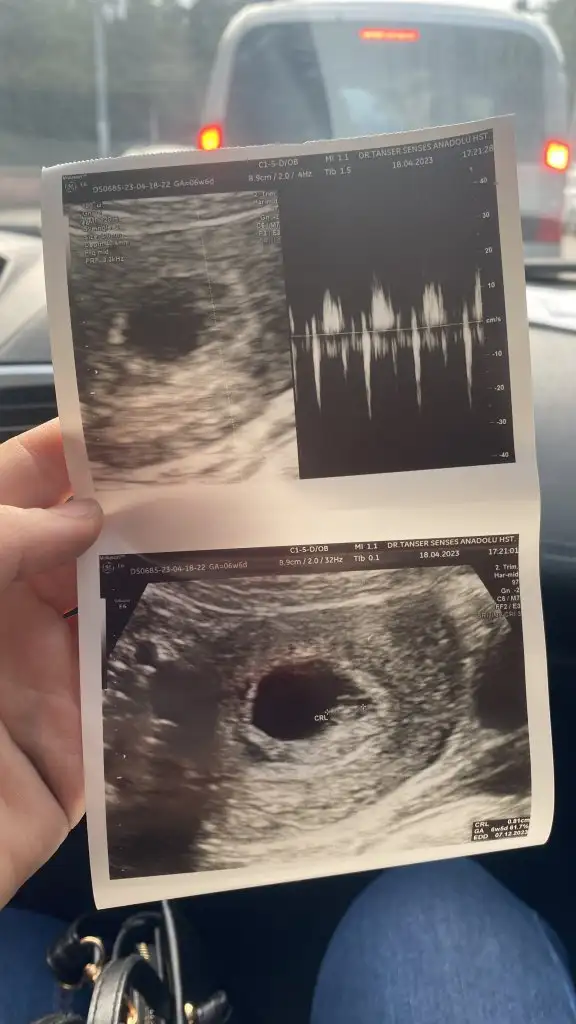

Kızlar selam ben 6+4 oldum ama ultrasonda 5+4 çıktı bugün kese var dedi bebek var gibi dedi cuma günü özele gitsem kalp atışını duyarmiyim

Bayada büyümüş kuzum istersen 12 haftalıkjen nub teorisine göre bakalım. Bu şekilde kıza benziyor plesentası sagda bebek solda duruyor. Ama bu haftalarda yanışma oluyor canım net olarak 6 haftalık oldugu zaman daha rahat tahminde bulunabiliyoruz

Böyle mi canım? Bu ultrasonda 6+6 yız bir daha ki ultrason 12ci haftamda